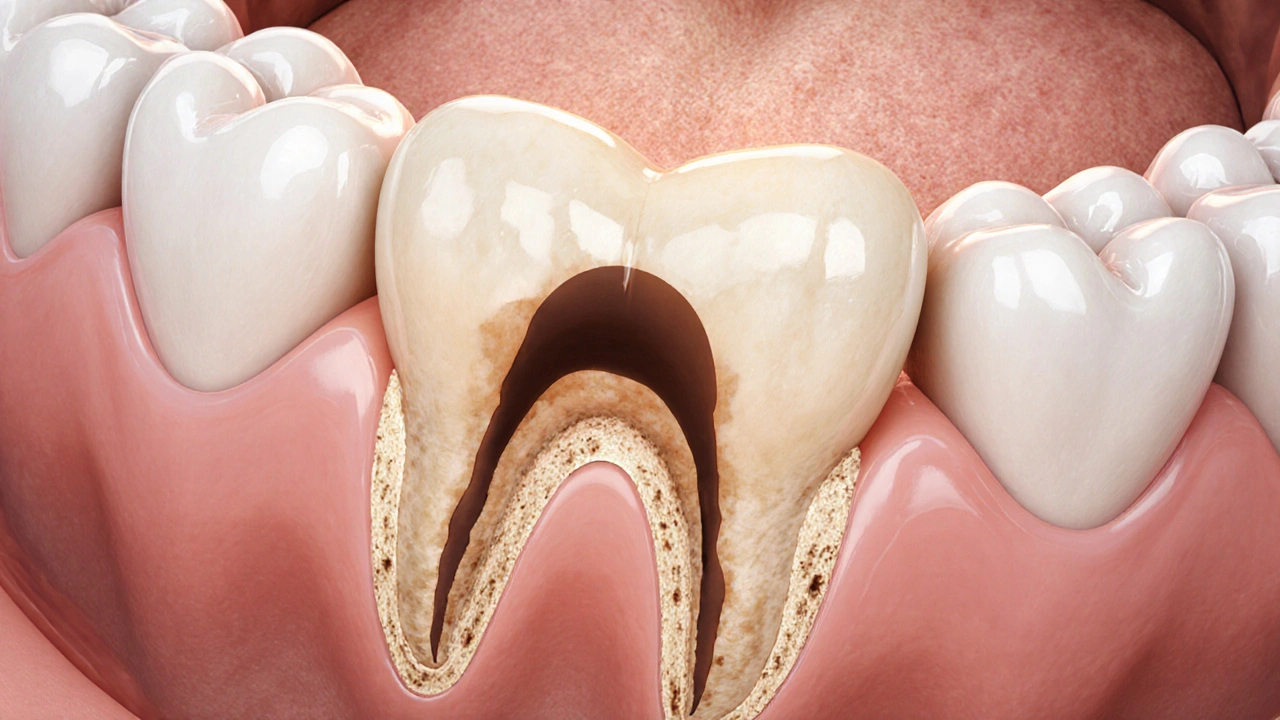

Zubní kaz začíná jako ztráta minerálů ve sklovině. Na začátku je to jen mírné oslabení, které rentgen ještě nezaznamená. Až když se kaz dostane do dentinu - vrstvy pod sklovinou - začne být na snímku vidět. Dentin je měkčí než sklovina, takže když ho kaz pronikne, vytvoří se v něm dutina, která je méně hustá. A méně hustá tkáň na rentgenu vypadá tmavěji.

Na panely rentgenového snímku se kaz obvykle objevuje jako tmavá skvrna, která se liší od okolní zubní tkáně. Tmavá oblast je větší než samotná dutina, protože rentgen zachycuje i okolní demineralizaci - místa, kde zub ztrácí minerály, ale ještě nevznikla plná dutina. Tato oblast se často rozšiřuje směrem k zubnímu nervu, a to je přesně ten okamžik, kdy se kaz stává vážným problémem.

Pokročilý kaz v dentinu směřující k zubnímu nervu na rentgenu.